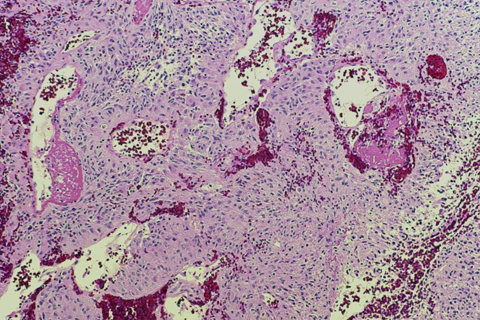

- To recognize neoplastic, non-tumorous and low-grade neuropathologic lesions and potential misdiagnosis

The material includes neoplastic and non-neoplastic entities from adults and children with specimens coming from the Johnnie L. Cochran, Jr. Brain Tumor Center, the Maxine Dunitz Neurosurgical Institute, the Pituitary Center and autopsy brains.

This one-month rotation includes an initial introduction to normal anatomy of the neuromuscular system, with subsequent weeks focused on CNS neoplasms, diseases of the muscles and nerves, and vascular, demyelinating, infectious and neurodegenerative disorders. Review of neuroimaging and correlation with the pathology is an integral aspect of the rotation. There is a comprehensive study set for review of all important neuropathologic lesions in addition to daily case review.